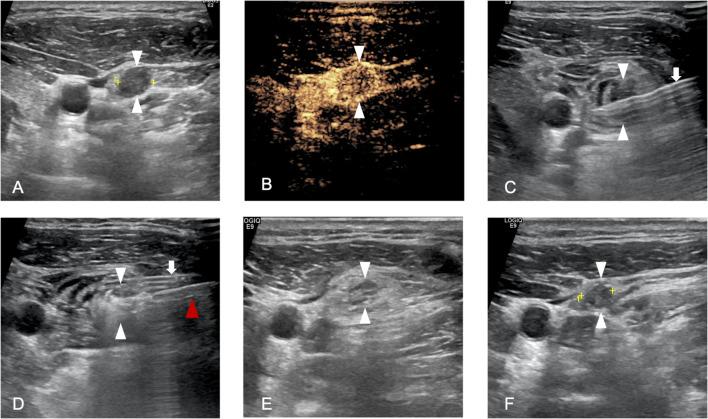

A total of 131 patients with 535 LNM from PTC who underwent ultrasound-guided MWA were included in the retrospective study. Patients were divided into three subgroups on the basis of treatment timing: initially treated, after PTC ablation (post-ablation), or after resection (post-resection). Changes in cervical metastatic lymph nodes as well as the incidences of complications, tumour recurrence and progression were compared.

The technical success rate of this study was 100% (535/535). Compared with those before MWA, the mean largest diameter and volume of the metastatic lymph nodes were significantly lower (p <0.01) at each follow-up. Transient hoarseness was the exclusive major complication with a total rate of 5.3% (9/171), which significantly differed in terms of incidence among the three subgroups (p<0.01). Lymph node location in region VI was an independent risk factor for transient hoarseness. The total recurrence rate was 22.8% (39/171) without statistically significant difference among the three sub-groups (p=0.20). Two cases received repeated surgery, while re-ablation was conducted successfully in all rest of cases. Data from the latest follow-up revealed one death due to LNM.